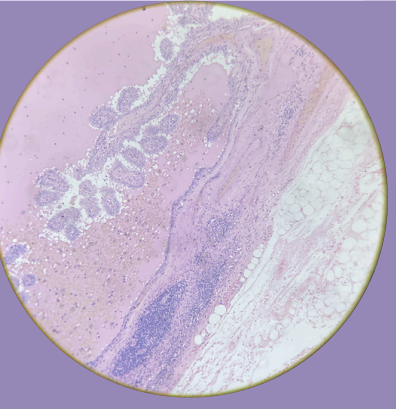

Carcinoma Papilar de Tiroides Metastásico a Ganglio Linfático:

Núcleos Orphan Anni

Presencia de proyecciones papilares

Células tumorales infiltrando el tejido del ganglio linfático